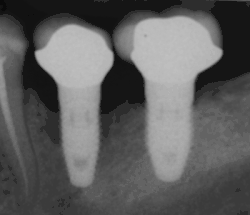

Od těchto teoretických rizik odvozujte komplikace v reálném světě. Dlouhodobá selhání jsou způsobena buď ztrátou kosti kolem zubu a/nebo dásně v důsledku periimplantitidy, nebo mechanickým selháním implantátu. Protože na implantátu není zubní sklovina, nedochází k jeho selhání v důsledku zubních kazů jako u přirozených zubů. Přestože rozsáhlých dlouhodobých studií není mnoho, několik systematických přehledů odhaduje dlouhodobou (pětiletou až desetiletou) životnost zubních implantátů na 93–98 % v závislosti na jejich klinickém použití.[1][2][3] Během počátečního vývoje zubních implantátů byly všechny korunky připevněny k zubům pomocí šroubů, ale novější pokroky umožnily umístění korunek na opěrky pomocí dentálního cementu (podobně jako při nasazování korunky na zub). Tím vznikla možnost, že cement, který unikne zpod korunky při cementaci, se zachytí v dásni a vytvoří periimplantitidu (viz obrázek níže). Ačkoli se tato komplikace může vyskytnout, nezdá se, že by u cementovaných korunek docházelo k dalším periimplantitidám ve srovnání se šroubovanými korunkami celkově.[59] U složených implantátů (dvoustupňových implantátů) jsou mezi vlastním implantátem a nadstavbou (abutmentem) mezery a dutiny, do kterých mohou pronikat bakterie z dutiny ústní. Později se tyto bakterie vrátí do přilehlých tkání a mohou způsobit periimplantitidu.